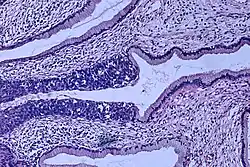

![Invasive squamous cell carcinoma of the cervix is characterized by infiltration as irregular anastomosing nests or single cells.[75] This case is poorly differentiated. H&E stain.](./_assets_/Histopathology_of_squamous_cell_carcinoma_of_the_cervix.png) Invasive squamous cell carcinoma of the cervix is characterized by infiltration as irregular anastomosing nests or single cells.[75] This case is poorly differentiated. H&E stain.

Invasive squamous cell carcinoma of the cervix is characterized by infiltration as irregular anastomosing nests or single cells.[75] This case is poorly differentiated. H&E stain. -